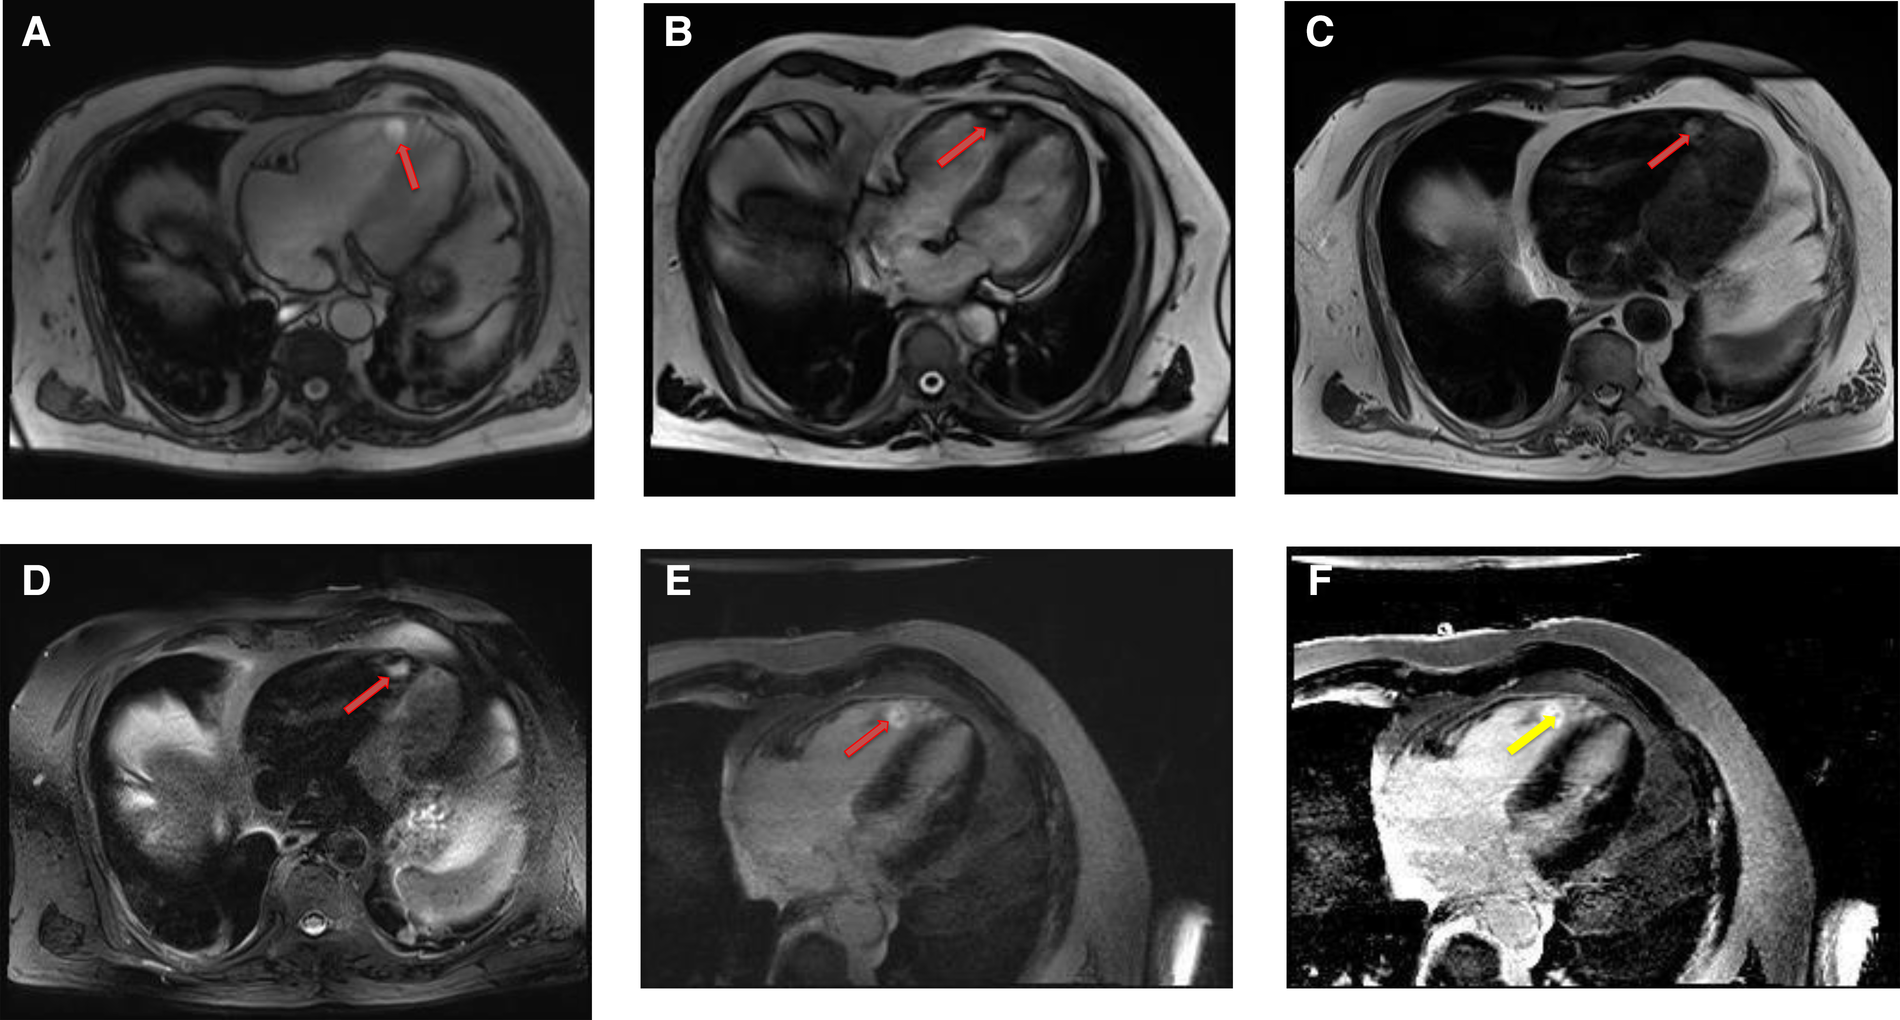

Lipomatous hypertrophy of the interatrial septum is a benign, non-encapsulated, nonneoplastic condition characterized by adipose cell hyperplasia in that region and is often found in older, overweight individuals (34). Lipomatous hypertrophy has the same signal characteristics as lipoma due to their fat content (35). However, lipomatous hypertrophy can be differentiated from lipoma by its morphologic features including larger than 2 cm size, typical involvement of the limbus of fossa ovalis that give rise to a characteristic “bilobed dumbbell appearance” (36) (Figures 5, 6). Most of the patients remain asymptomatic, but there are reported cases of atrial arrhythmias.

Figure 5

A 53-year-old male with lipomatous hypertrophy of the intra-atrial septum. (A) Cine CMR images showing diffuse enlargement and fatty replacement of the intra-atrial septum, consistent with lipomatous hypertrophy of the intra-atrial septum (red arrow). (B) Characteristic “dumbbell shaped” appearance of the mass on axial dark blood, double inversion recovery fast spin echo images (red arrow).

Figure 6

A 61-year-old male with lipomatous hypertrophy of the intra-atrial septum. (A) Cine CMR images showing diffuse enlargement and fatty replacement of the intra-atrial septum, consistent with lipomatous hypertrophy of the intra-atrial septum (red arrow). (B) Characteristic “dumbbell shaped” appearance of the mass on axial dark blood, double inversion recovery fast spin echo images (red arrow).

4.2.1. Cardiac MRI features

CMR provides a definitive diagnosis of both lipoma and lipomatous hypertrophy. Lipomas typically have a homogeneous appearance on CMR. Characteristically, they have the same signal intensity as surrounding chest wall fat on both T1- and T2-weighted images. Additionally, two extremely useful sequences are pre and post contrast fat saturated T1 Weighted sequences. Characteristically, signal dropout is observed on these sequences confirming the diagnosis of a fat-containing lesion. Due to their avascular nature, they do not show contrast enhancement on LGE images (Table 1 and Figures 7, 8).

Figure 7

A 68-year-old female with intra-atrial septal lipoma. (A) (On line video 3), CMR cine images showing a sharply marginated mass arising from the intraatrial septum (red arrow). (B) This mass has same signal intensity (high) as surrounding fat on axial T1-weighted, dark blood, double inversion recovery fast spin echo images (red arrow). (C) Fat suppression sequence representing suppression of surrounding fat (white arrow) as well as the mass in the intra-atrial septum (red arrow).

Figure 8

A 50-year-old female with intra-atrial septal lipoma. (A) This mass has signal intensity (high) as surrounding fat on axial T2-weighted, dark blood, double inversion recovery fast spin echo images (red arrow). (B) This mass is suppressed on axial triple inversion recovery images (red arrow). (C) Complete absence of contrast agent uptake on late gadolinium enhanced images (red arrow).